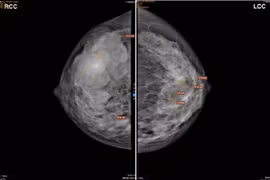

Sờ thấy có khối u ở vú phải, khối u này to dần theo thời gian, mật độ chắc, đau khi gần đến chu kỳ kinh… người phụ nữ đi khám bất ngờ được chuẩn đoán mắc u diệp thể tuyến vú hiếm gặp.

Ung thư vú là nguyên nhân gây tử vong hàng đầu trong các loại ung thư ở phụ nữ trên thế giới. Tuy nhiên, có một số nhóm người có nguy cơ cao mắc ung thư vú.